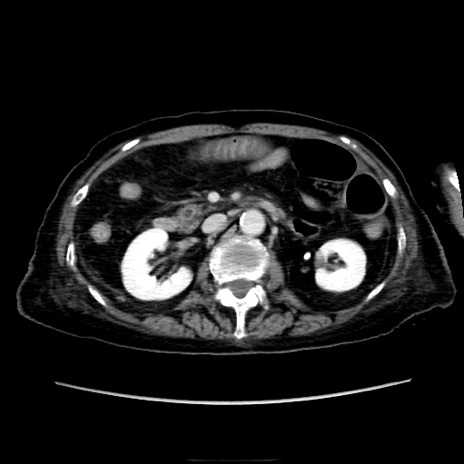

他院CT

横断像